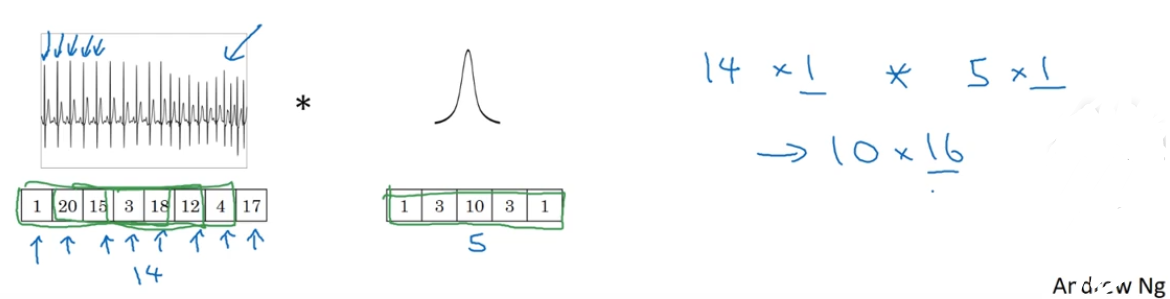

事实证明这些想法也同样可以用于1维数据,举个例子,左边是一个EKG信号,或者说是心电图,当你在你的胸部放置一个电极,电极透过胸部测量心跳带来的微弱电流,正因为心脏跳动,产生的微弱电波能被一组电极测量,这就是人心跳产生的EKG,每一个峰值都对应着一次心跳。

如果你想使用EKG信号,比如医学诊断,那么你将处理1维数据,因为EKG数据是由时间序列对应的每个瞬间的电压组成,这次不是一个14×14的尺寸输入,你可能只有一个14尺寸输入,在这种情况下你可能需要使用一个1维过滤进行卷积,你只需要一个一维的过滤器,而不是一个5×5的。

二维数据的卷积是将同一个5×5特征检测器应用于图像中不同的位置,你最后会得到10×10的输出结果。1维过滤器可以取代你的5维过滤器,可在不同的位置中应用类似的方法。

再一次如果你使用多通道,在这种场景下可能会获得一个14×1的通道。如果你使用一个EKG,就是5×1的,如果你有16个过滤器,可能你最后会获得一个10×16的数据,这可能会是你卷积网络中的某一层。

对于卷积网络的下一层,如果输入一个10×16数据,你也可以使用一个5维过滤器进行卷积,这需要16个通道进行匹配,如果你有32个过滤器,另一层的输出结果就是6×32,如果你使用了32个过滤器的话。

所有这些方法也可以应用于1维数据,你可以在不同的位置使用相同的特征检测器,比如说,为了区分EKG信号中的心跳的差异,你可以在不同的时间轴位置使用同样的特征来检测心跳。